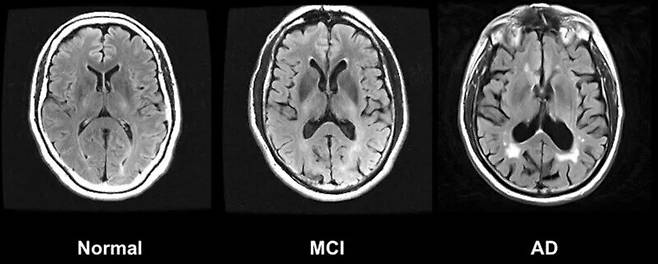

2021년 기준으로 전 세계에서 6900만명이 알츠하이머병, 파킨슨병 같은 신경퇴행성 질환을 앓고 있다. 게다가 이들 질환자 수는 20년마다 두 배로 증가할 것으로 예상돼 전 세계적인 보건 문제로 떠올랐다. 세계보건기구(WHO)에 따르면 치매는 이제 전 세계 사망 원인 7위로 올라섰다. 70살 이상에선 사망 원인 4위다. 그러나 아직도 질병이 일어나는 기전이 명확히 규명되지 않아 효과적인 치료법이 나오지 않은 상황이다.

단백질 데이터는 전 세계 23개 연구기관에서 제공한 혈장, 뇌척수액 등의 생체 시료를 분석한 것이다. 연구진은 이 데이터가 주요 신경퇴행성 질환의 조기 진단 및 예후 개선에 도움을 줄 것으로 기대했다. 신경퇴행성 질환과 관련된 단백질을 분석하면 신경퇴행의 복잡한 분자적 구조를 밝혀낼 수 있다.

이번 연구에서 미국 세인트루이스 워싱턴대 의대의 카를로스 크루차가 교수가 중심이 된 연구진은 알츠하이머병, 파킨슨병 및 전두측두엽 치매에서 질병 특이적 혈장 생체표지와 단백질 특징을 확인하고, 진단 및 치료 전략에 활용할 수 있는 조절 단백질과 메카니즘을 밝혀냈다.

미국 스탠퍼드대의 토니 와이스-코레이 교수가 중심이 된 연구진은 인지 기능과 상관관계가 있는 단백질이 나이가 들면서 어떻게 변화하는지 밝혀냈다. 연구진은 뇌척수액과 혈장의 단백질 수치 변화와 인지 건강의 연관성을 밝히는 새 단서가 될 것으로 기대했다.